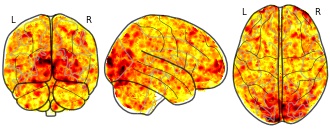

Individual Brain Charting dataset extension, second release of...

EmailClick to copy linkLink copied Cite(2020). Individual Brain Charting dataset extension, second release of high-resolution fMRI data for cognitive mapping: sub-06_ses-02_task-hcp_wm_ffx_2back_face [Dataset]. http://identifiers.org/neurovault.image:368774niftiAvailable download formatsUnique identifierhttps://identifiers.org/neurovault.image:368774Dataset updatedFeb 15, 2020License

Cite(2020). Individual Brain Charting dataset extension, second release of high-resolution fMRI data for cognitive mapping: sub-06_ses-02_task-hcp_wm_ffx_2back_face [Dataset]. http://identifiers.org/neurovault.image:368774niftiAvailable download formatsUnique identifierhttps://identifiers.org/neurovault.image:368774Dataset updatedFeb 15, 2020LicenseCC0 1.0 Universal Public Domain Dedicationhttps://creativecommons.org/publicdomain/zero/1.0/

License information was derived automaticallyDescriptionCollection description

The individual Brain Charting (IBC) Project is using high resolution fMRI to map 13 subjects that undergo a large number of tasks: the HCP tasks, the so-called ARCHI tasks, a specific language task, video watching, low-level visual stimulation etc. The native resolution of the data is 1.5mm isotropic. Their main value lies in the large number of contrasts probed, the level of detail and the high SNR per subject. This dataset is meant to provide the basis of a functional brain atlas. We upload here smoothed individual SPMs. The uploaded maps comprise session-specific and fixed effects across maps acquired with AP and PA phase encoding directions.

Note that Neurovault collection #4438 is a subset of that one. In the present collections, some details have been fixed, including mroe accurate and unique file naming.

Subject species

homo sapiens

Modality

fMRI-BOLD

Analysis level

single-subject

Cognitive paradigm (task)

working memory fMRI task paradigm

Map type

Z